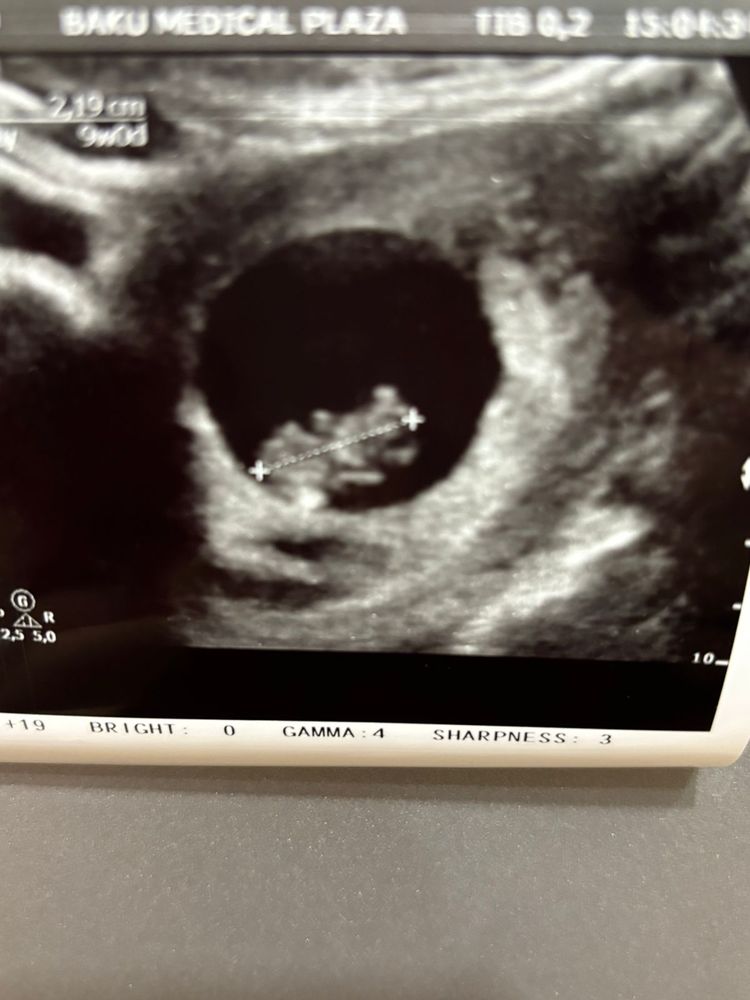

Я БЕРЕМЕННА !Ну чтож, сходили сегодня на очередное УЗИ, срок нам поставили 9 недель 4 дня, сердцебиение 178 ударов в минуту, малютка активно шевелится😍

У малыша уже видно ручки и ножки, совсем уже человечек 🩷

Есть и печальный момент две немаленькие такие гематомы, снизу и справа от ПЯ, 13,5мм и 11мм... У нас с гематомами не кладут на сохранение...Назначили ударную дозу прогика и строго наказали лежать пластом 😔